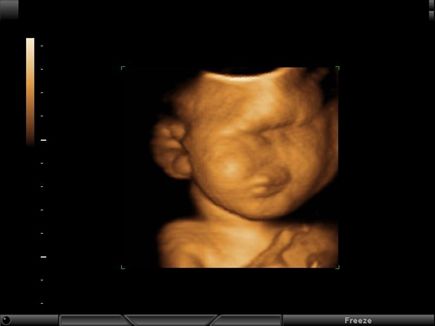

Challenge your diagnostic skills: Can you identify this anomaly of the fetal face and brain?